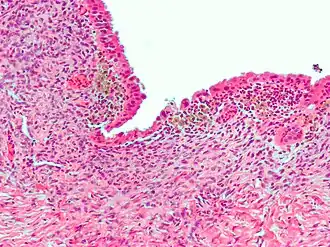

| Micrografia mostrando endometriose (coloração H&E), uma causa comum de dor pélvica crônica em mulheres. | |